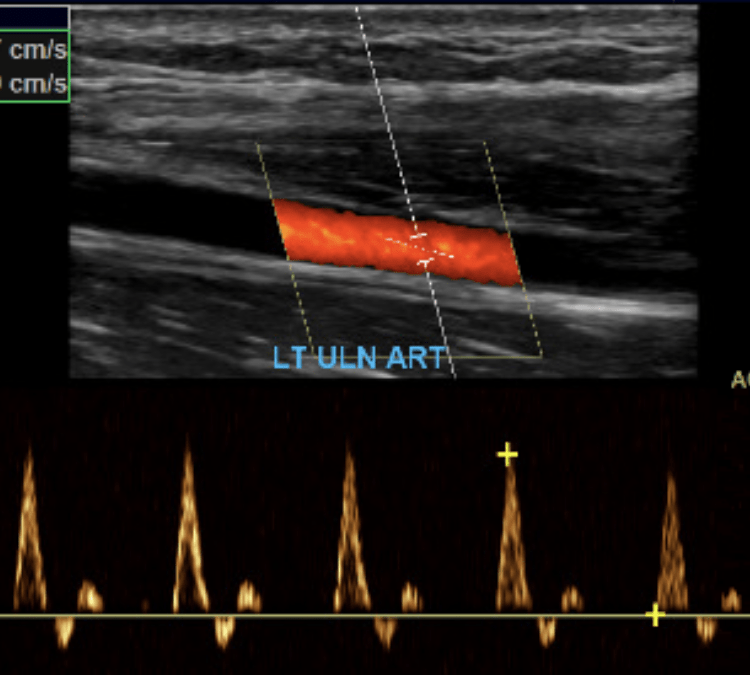

The subclavian artery arises from the brachiocephalic artery on the right and off of the aortic arch on the left. This artery further divides into the axillary, brachial, radial, ulnar, palmar and digital arteries respectively.